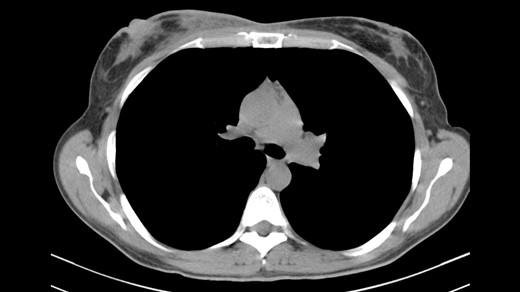

Due to the above findings, computed tomography (CT) (Fig. 3) and magnetic resonance imaging (MRI) were obtained. An MRI reported an area of 9.6 × 5 × 7.3 mm in the right breast enhanced by contrast uptake. The process infiltrated a segment of the overlying skin, and the MRI was labeled as Breast Imaging Reporting and Data System (BIRADS) category 4C (Fig. 4); therefore, a biopsy was requested.

CT indicating heterogeneous enhancement and diffuse thickening of the skin of the right breast.